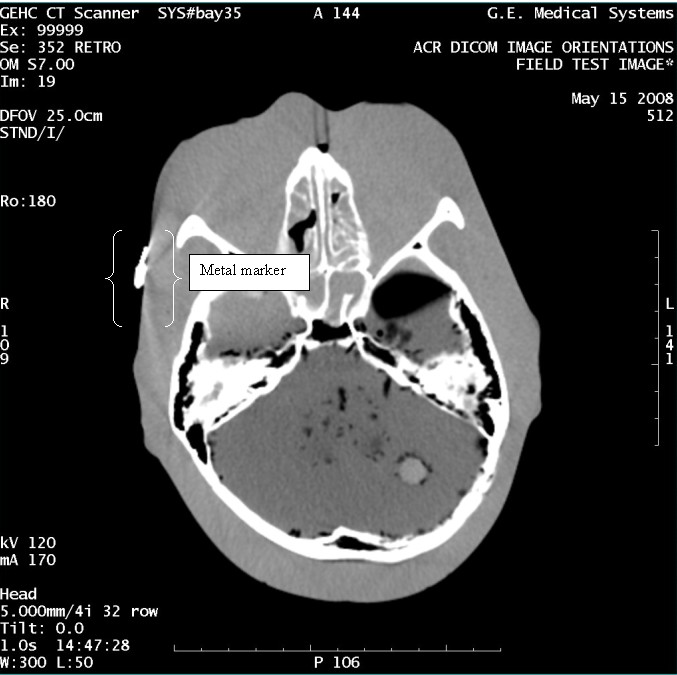

- With the support of the site personnel, examine the images sent

to the Review Station (i.e., 12 series, each with 1 image) and compare

their orientation to the images in this document.

- Each image contains a metal marker on the phantom's right cheek.

- Each image in this document contains a description of the expected

orientation of the metal marker (i.e. to prove Left and Right) as

well as the Posterior and Anterior orientation description.note:

The sample images included in this document use “R”, “L”, “P”, and “A” for “Right”, “Left”, “Posterior” and “Anterior” orientation. The Hospital Review Station may use a different style of annotation. The style used is not relevant to this procedure.

- Each image in this document has sufficient space to store the observed results for up to 4 Review Stations.

- Enter ‘Y’ in the space to indicate the observed result matches the expected.

- Enter ‘N’ in the space to indicate the observed result does not match the expected.

- Enter “NA” in the space if a column is not being used.

- Repeat for each destination.

Figure 11. Exam 99999, Series 352